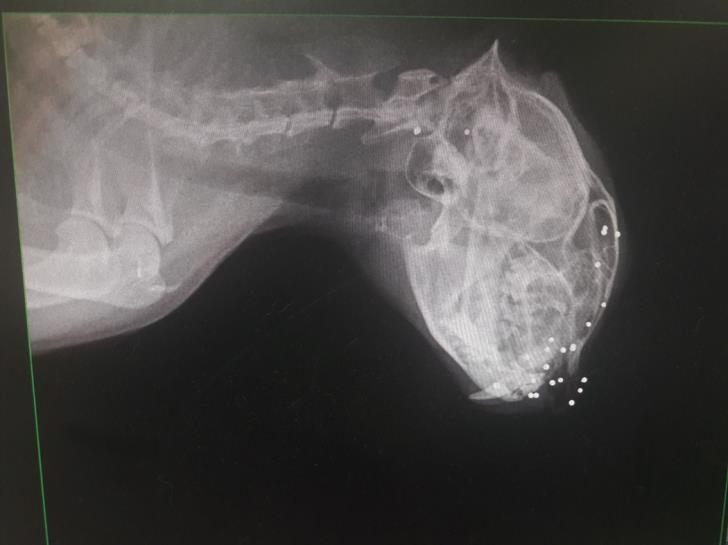

Σε ανακοίνωσή του το Κόμμα δημοσιεύει φωτογραφίες για επιθέσεις σε ζώα με αεροβόλο και εκφράζει τις απορίες: